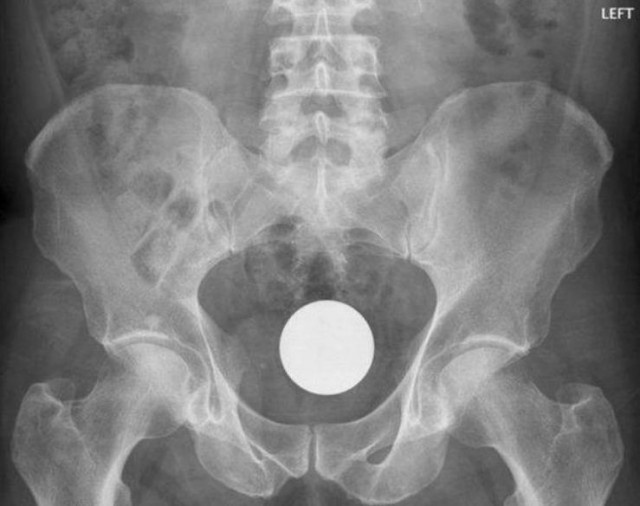

・ビリヤードの球、この中では割と王道?